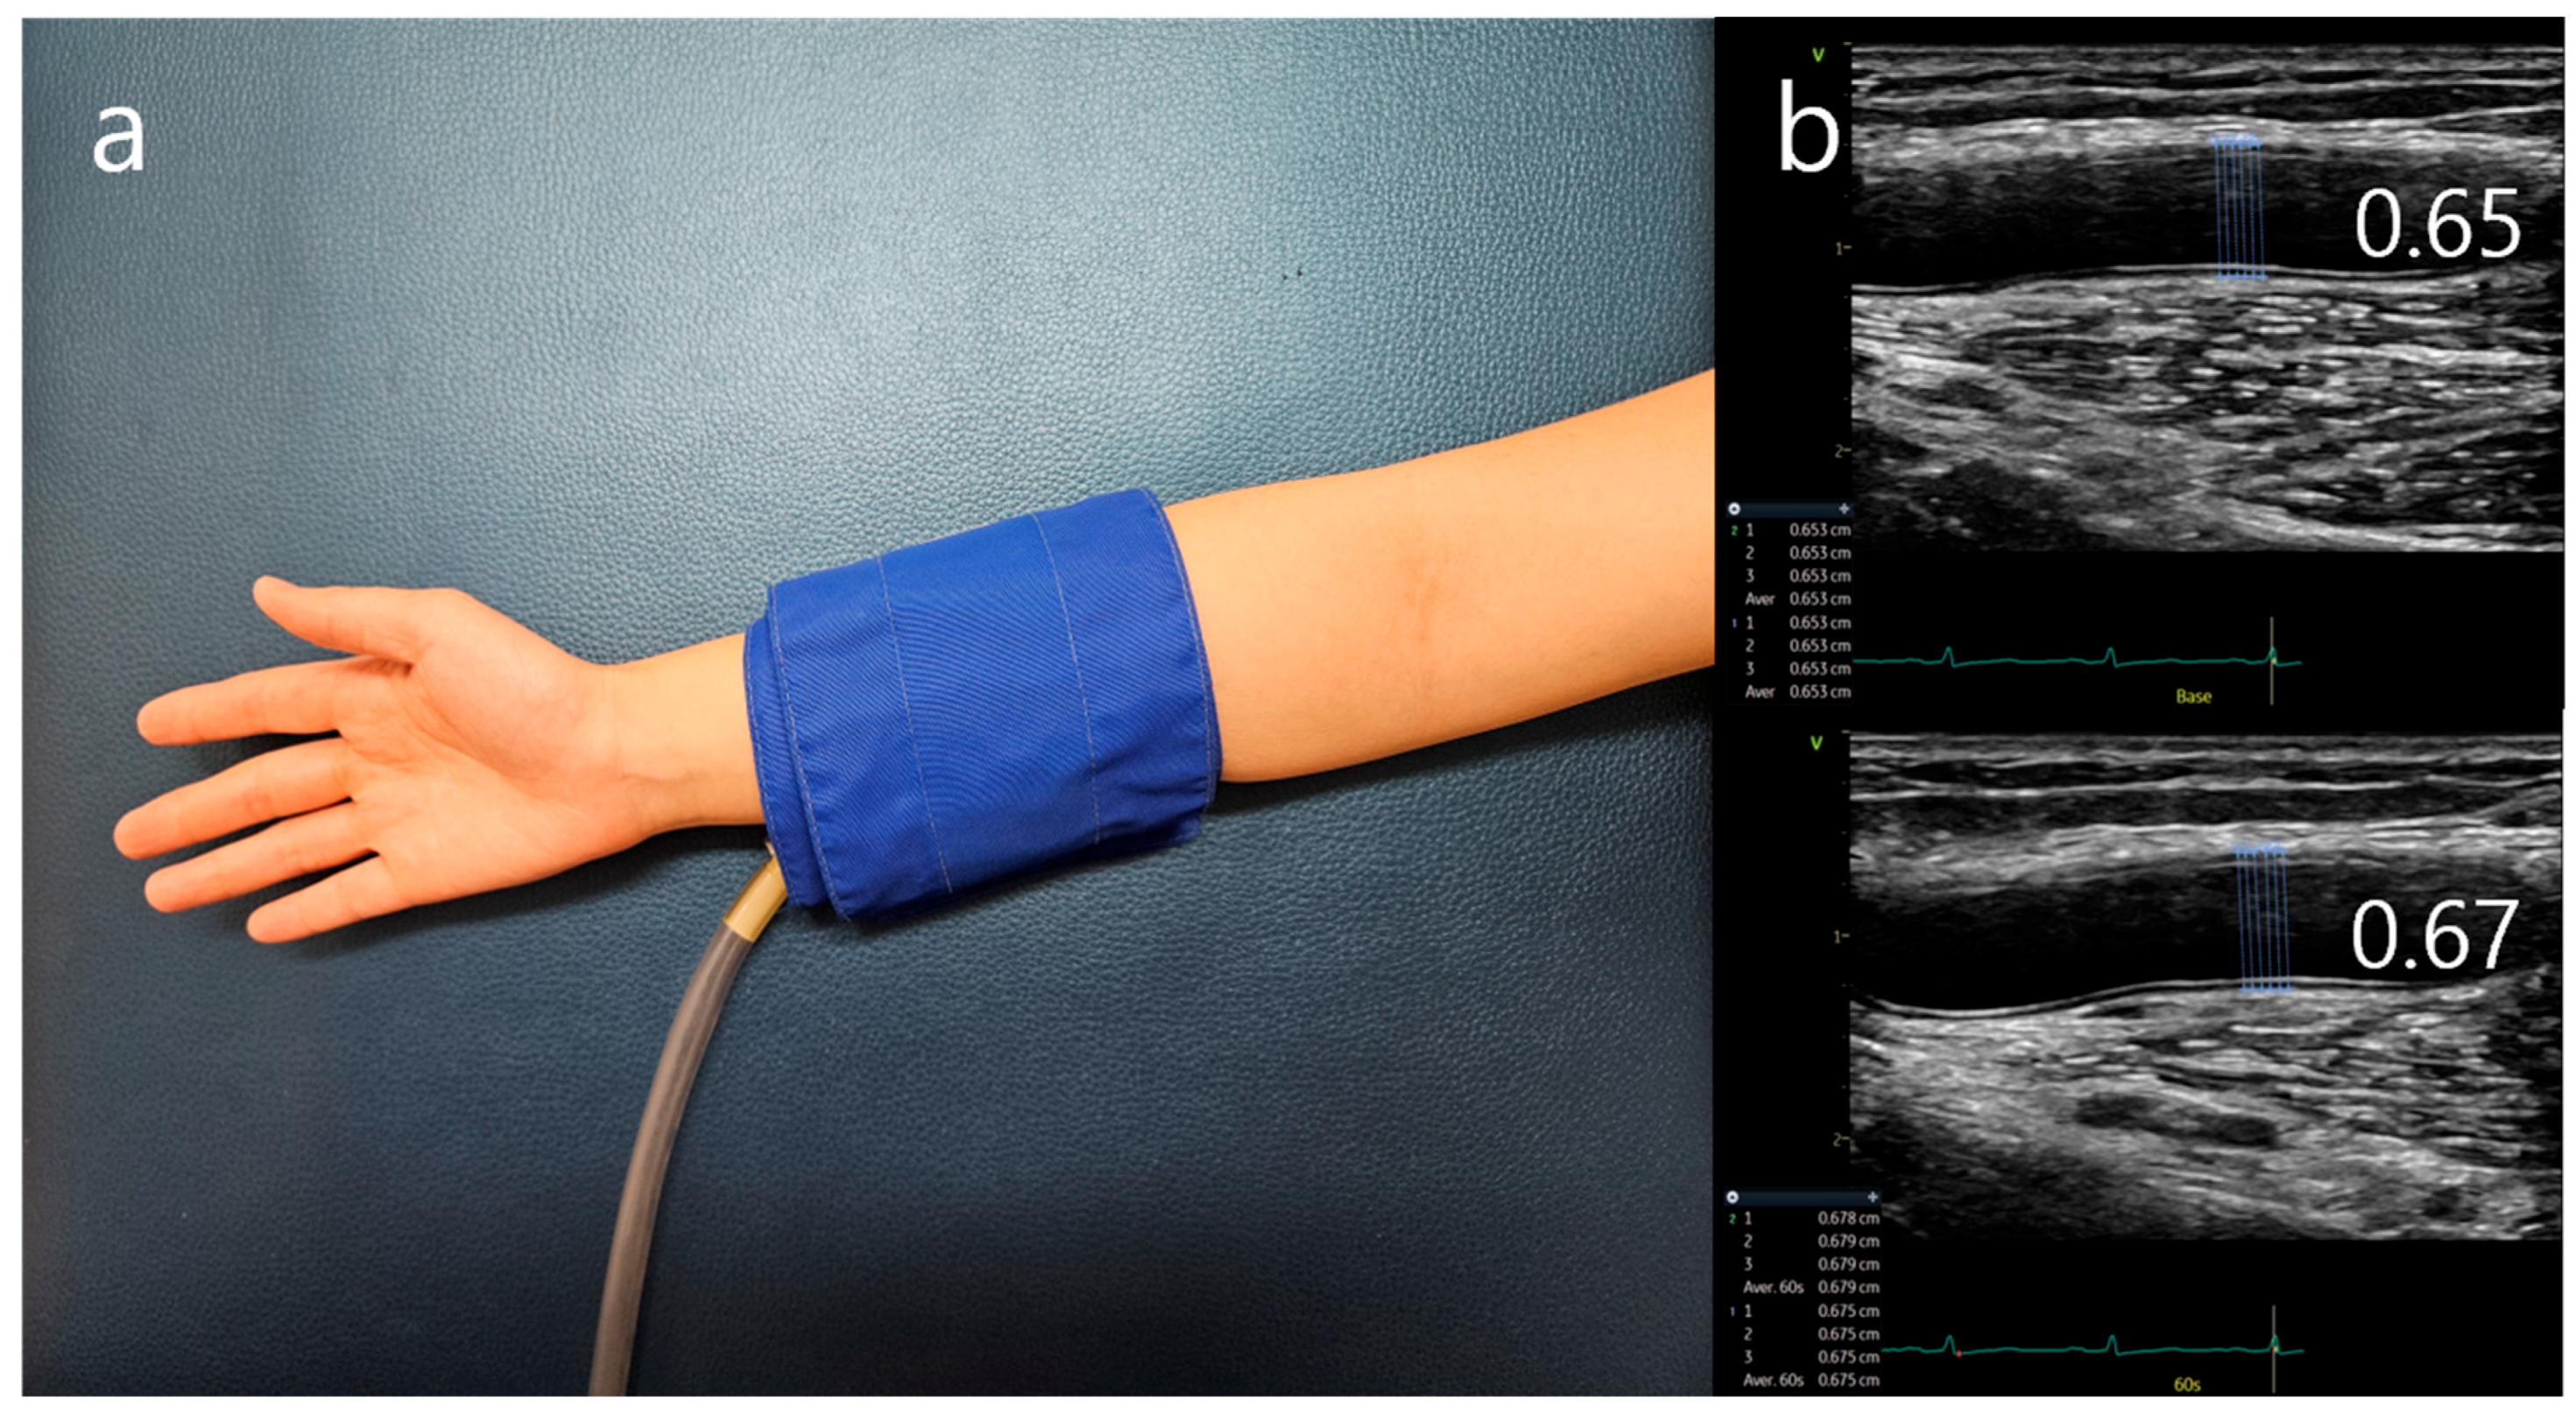

3. Assessment of FMD

Methodological Issues